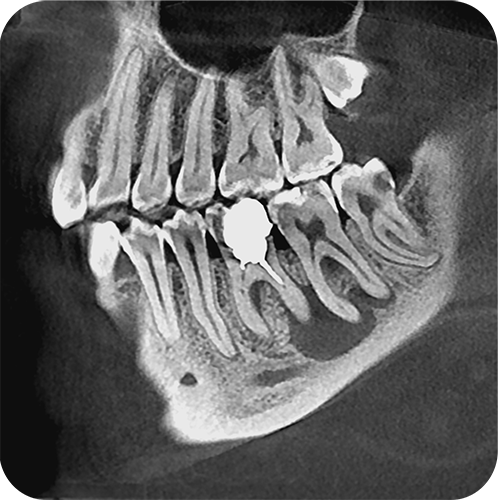

На выставке «Дентал Экспо Красноярск» успешно прошло заседание главных врачей во главе с Садовским Владимиром Викторовичем, Вице-президентом Общества Врачей России, Почетным Президентом СтАР, Директором Национального института исследований и адаптации маркетинговых стратегий (НИИАМС). Помимо насущных вопросов, руководители организаций региона обсудили преимущества и возможности использования стоматологического томографа Genoray Papaya 3D.

- Уникальный моторизованный подбородочный упор с автоматическим позиционированием головы пациента в зависимости от типа и зоны исследования. Достаточно выбрать зону интереса. Все остальное делает сам аппарат!

- Плоскопанельный детектор имеет самую высокую в классе разрешающую способность